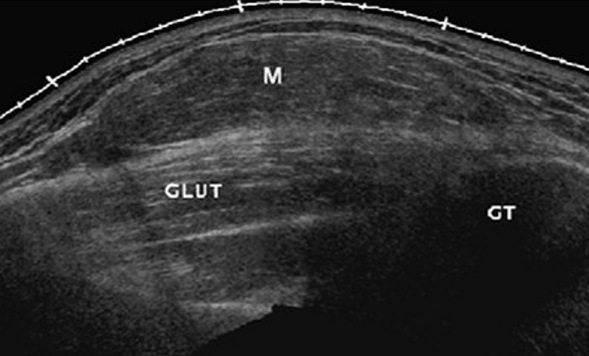

肌骨超声介绍 肌肉、骨骼、神经及关节系统的超声应用是近几年国际超声医学领域研究的热点之一,覆盖范围涉及运动医学、骨科学、康复医学、风湿免疫学及神经病学等。 目前,高频超声探头具有很高的分辨率,可清晰显示肌腱、肌肉、滑囊、神经、软骨等组织的正常结构和损伤程度。高频超声对软组织病变的显示能力,可与核磁共振相媲美。能够精细分辨肌肉、浅表神经的解剖结构。 肌骨超声的检查优势 价格低廉、无创、便捷、可复性强,特别适宜于妇女和儿童,能够对肌肉、肌腱的运动实验进行实时动态观察的独特优势,无明确禁忌症,无辐射、无特需准备,操作简便。 肌骨超声的检查范围 肌肉、肌腱、韧带、关节、滑囊、周围神经、骨、软骨、皮肤及皮下软组织。 肌骨超声已广泛应用于临床,目前齐齐哈尔附属第三医院彩超室引进飞利浦、日立、GE等高档彩超仪,可以开展肌骨超声检查,主要用于评价皮肤、筋膜、肌肉、肌腱、韧带和周围神经、肌骨关节等,可以用超声诊断出肢体肿物、肌腱炎、肌腱损伤、肌腱断裂、腱鞘炎、滑囊炎、滑膜炎、滑膜囊肿、韧带撕裂、损伤、神经卡压、肌肉损伤、骨折、关节肿胀以及类风湿关节炎、痛风等累及关节病变,并可与骨科、内分泌、风湿科、康复科、疼痛科等开展多学科临床治疗协作。 几种典型肌骨超声图片: 肌肉撕裂:为临床中较常见的疾病,主要跟运动相关。很多的时候患者可能在运动过程当中,突然感听到一个声音从前臂、小腿、大腿部位发出来;或者有的病人运动过程中自觉突然有人踢他,但并没有人触碰到他,这时患者会出现功能受限,局部疼痛等情况。